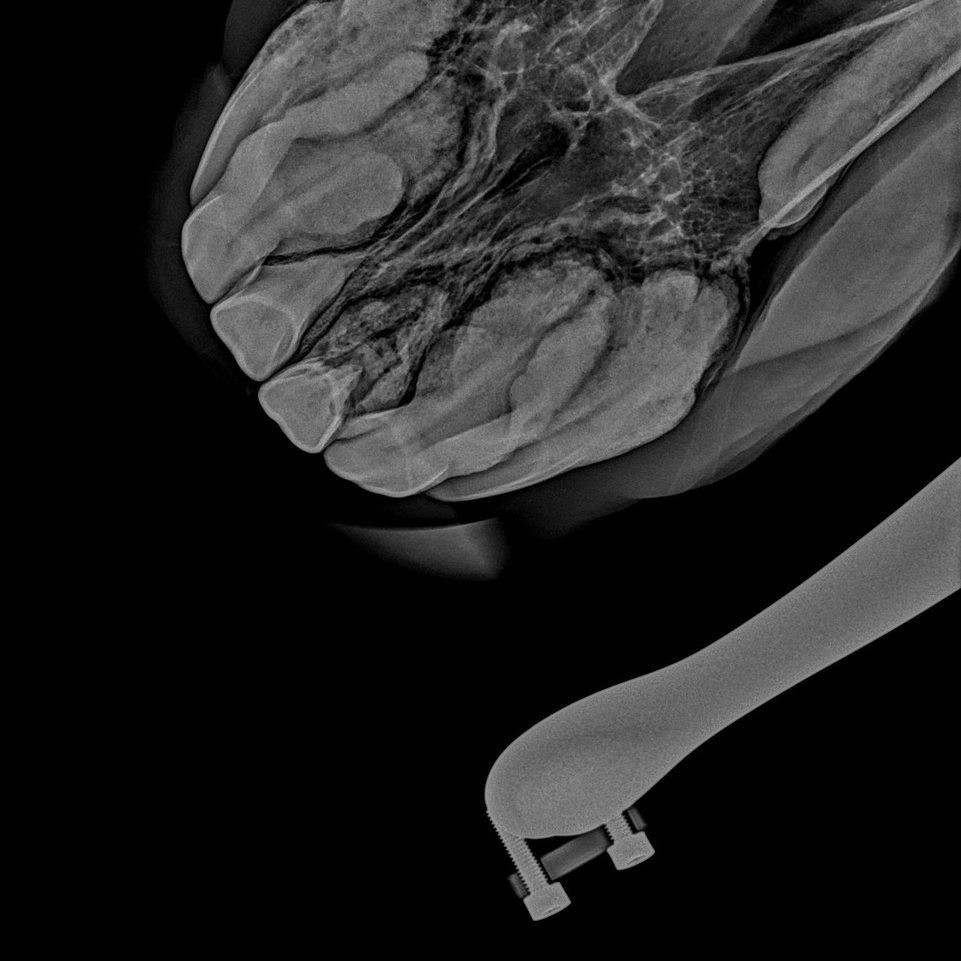

Insbesondere bei älteren Pferden wird häufig eine EOTRH (Equine Odontoclasic Tooth – Resorption and Hypercementosis) diagnostiziert. Es kommt dabei zu zahnauflösenden und knochenumbauenden Prozessen im Wurzelbereich der Schneide- und Eckzähne. Symptome dieser Erkrankung können sein:

• Probleme beim Abbeißen von hartem Brot oder Möhren

• Trinken von kaltem Wasser ist unangenehm

• kleine Eiterbläschen oder auch nur kleine rote Punkte im Zahnfleisch

• verdicktes wulstiges rotes Zahnfleisch, Zahnfleischrückgang

• vermehrte Zahnsteinbildung